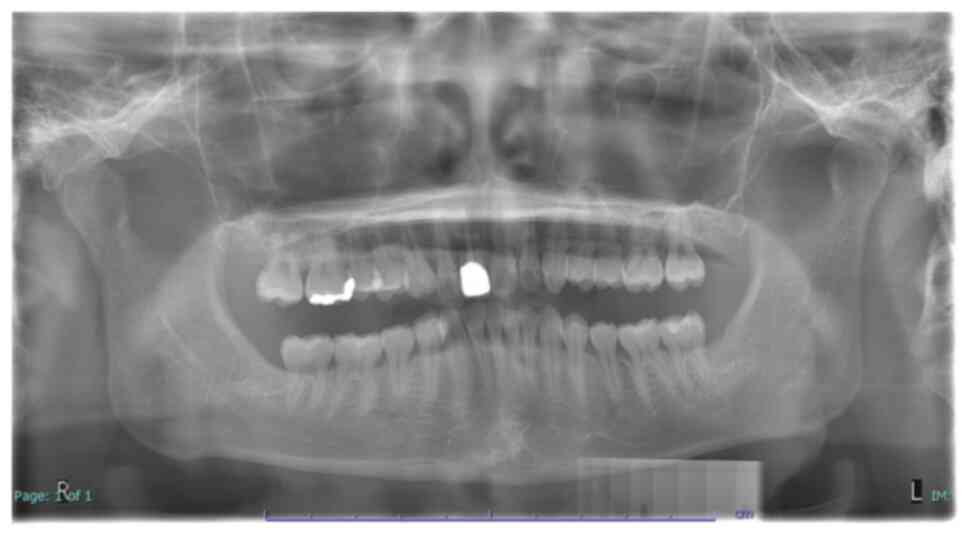

Oral/dental surgical care in patients with chronic medical comorbidities, such as isovaleric acidemia (IVA), can be challenging. In addition to technical complications, different comorbidities also present a complex range of concerning factors/challenges, which can increase the incidence of morbidity and mortality associated with surgery. IVA, a congenital error of metabolism, is a rare organic acidemia with a predisposition towards acute acidosis and life‑threatening metabolic decompensation during stressful conditions, such as prolonged fasting and surgery. In addition, schizophrenia, a major neurological disorder, can result in manifestation of severe dental or periodontal conditions, including pericoronitis. The condition is associated with significant risk factors of postoperative complications, such as dangerous behaviors and adverse interactions between antipsychotic drugs and anesthetic agents. A case of comorbid dental disease with two coexisting chronic and life‑threatening medical conditions, one of which is rare, is an unusual encounter in oral/dental surgery that is seldomly published. Moreover, implementing a safe and effective surgical intervention in such patients requires several informed considerations. However, only a few reported experiences or guidelines exist, reporting appropriate perioperative management strategies to minimize risks. Hence, in this case report, our experience of managing one of these rare encounters of a 20‑year‑old man who suffered from bilaterally partially erupted third molars, associated with chronic pericoronitis and dental caries of both the maxilla wisdom teeth with coexisting IVA and schizophrenia comorbidities is described. Additionally, the presentation and anticipated complications of the comorbid disorders of the patient are briefly reviewed. In this case, the pericoronitis and dental caries were treated by surgically removing the impacted third molars and the antagonist maxilla wisdom teeth under regional anesthesia and application of antibiotics for 3 days. The patient recovered without any postoperative complications after 1 year of follow‑up.

Figure 1

Figure 2

Figure 3

Figure 4